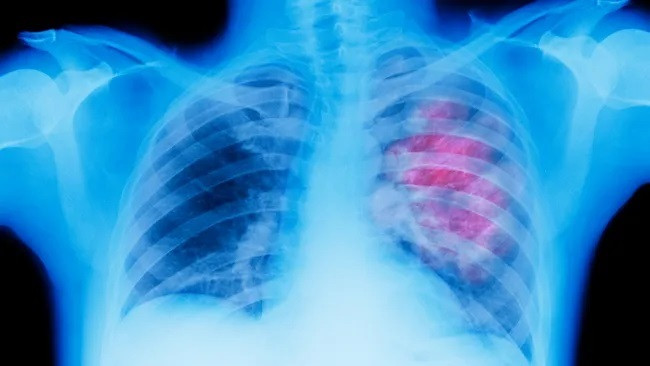

| Chỉ bằng xét nghiệm X-quang, chương trình Trí tuệ nhân tạo có thể phát hiện sớm nguy cơ cao mắc ung thư phổi ở những người không hút thuốc lá. |

Trong nghiên cứu mới, các nhà nghiên cứu đã thử nghiệm mô hình AI, được đặt tên là "Rủi ro phổi CXR" trên hàng nghìn bức ảnh chụp X-quang ngực của những người không hút thuốc trong độ tuổi từ 55 đến 74. AI đã xác định được 28% có nguy cơ cao mắc bệnh ung thư phổi.

Trong nhóm có nguy cơ cao này, gần 3 trong 100 người mắc bệnh ung thư phổi trong vòng 6 năm - cao hơn gấp đôi ngưỡng tối thiểu đưa ra khuyến nghị sàng lọc. Các nhà nghiên cứu đã trình bày kết quả của họ tại cuộc họp thường niên của Hiệp hội X quang Bắc Mỹ (RSNA), diễn ra từ ngày 26-30/11 vừa qua.

CXR Lung-Risk là một mô hình học sâu, bằng cách nhận dạng các mẫu và từ trải nghiệm của chính hệ thống khi di chuyển dữ liệu giữa nhiều lớp mạng lưới thần kinh. Các nhà nghiên cứu đã huấn luyện thuật toán này với 147.497 ảnh chụp X-quang ngực của 40.643 người hút thuốc không có triệu chứng cũng như những người không hút thuốc từ Thử nghiệm sàng lọc ung thư tuyến tiền liệt, phổi, đại trực tràng và buồng trứng (PLCO) diễn ra từ năm 1993 đến năm 2001. Một số người trong số này đã tiếp tục phát triển ung thư phổi trong vòng sáu năm kể từ khi đưa vào thử nghiệm.

Sau đó, AI xem xét các ảnh chụp X-quang, được chụp từ năm 2013 đến năm 2014, từ 17.407 người không hút thuốc để xác định khả năng chẩn đoán trong tương lai, phân loại bệnh nhân thành các nhóm có nguy cơ thấp, trung bình và cao.

2,9% bệnh nhân trong nhóm có nguy cơ cao tiếp tục phát triển ung thư phổi cao gấp 2,1 lần so với nhóm có nguy cơ thấp. Họ cũng vượt quá ngưỡng rủi ro 1,3% khi đưa ra khuyến nghị sàng lọc.